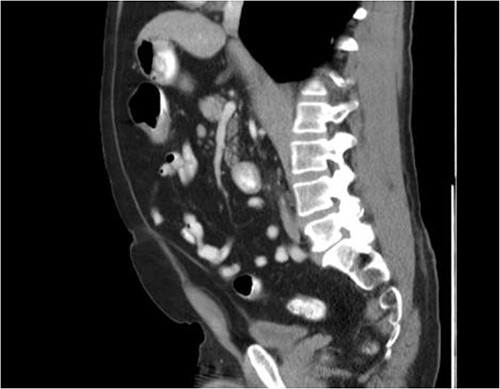

He was then referred to gastroenterology and underwent diagnostic colonoscopy that showed a large polypoid mass in the transverse colon that was partially obstructing. Gastroenterology then obtained a CT scan of the chest, abdomen and pelvis that showed wall thickening of the colon (Figs 1–3). Ultimately when pathology confirmed malignant melanoma, a PET scan was ordered that showed increased uptake at the previously seen and biopsied transverse colon mass (Fig. 4).

Axial CT scan with IV contrast showing thickened transverse colon.